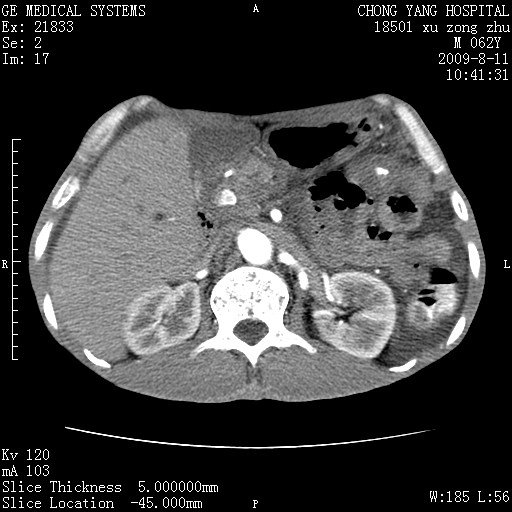

以下是引用杀毒软件在2009-8-11 16:35:00的发言:[br]肝内胆管扩张局限于左叶,胆管内有结石伴肝外胆管结石,胆管壁增厚呈弥漫性并发腹腔积液,胰腺边界模糊。[br][br]考虑---胆总管及肝内胆管结石继发胆管炎及胰腺炎,左肾下极囊肿,腹水。

以下是引用zjzjr在2009-8-11 17:35:00的发言:[br]肝内胆管扩张局限于左叶,胆管内有结石伴肝外胆管结石,胆管壁增厚呈弥漫性并发腹腔积液。[br][br]考虑---胆总管及肝内胆管结石继发胆管炎,左肾下极囊肿,腹水。